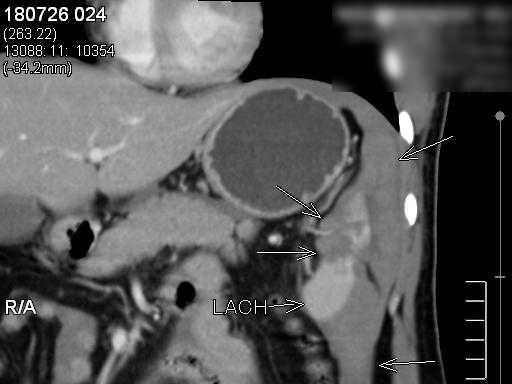

![]() |

| Một phần nhỏ của dị vật sau khi được gắp ra. Ảnh: BVCC |